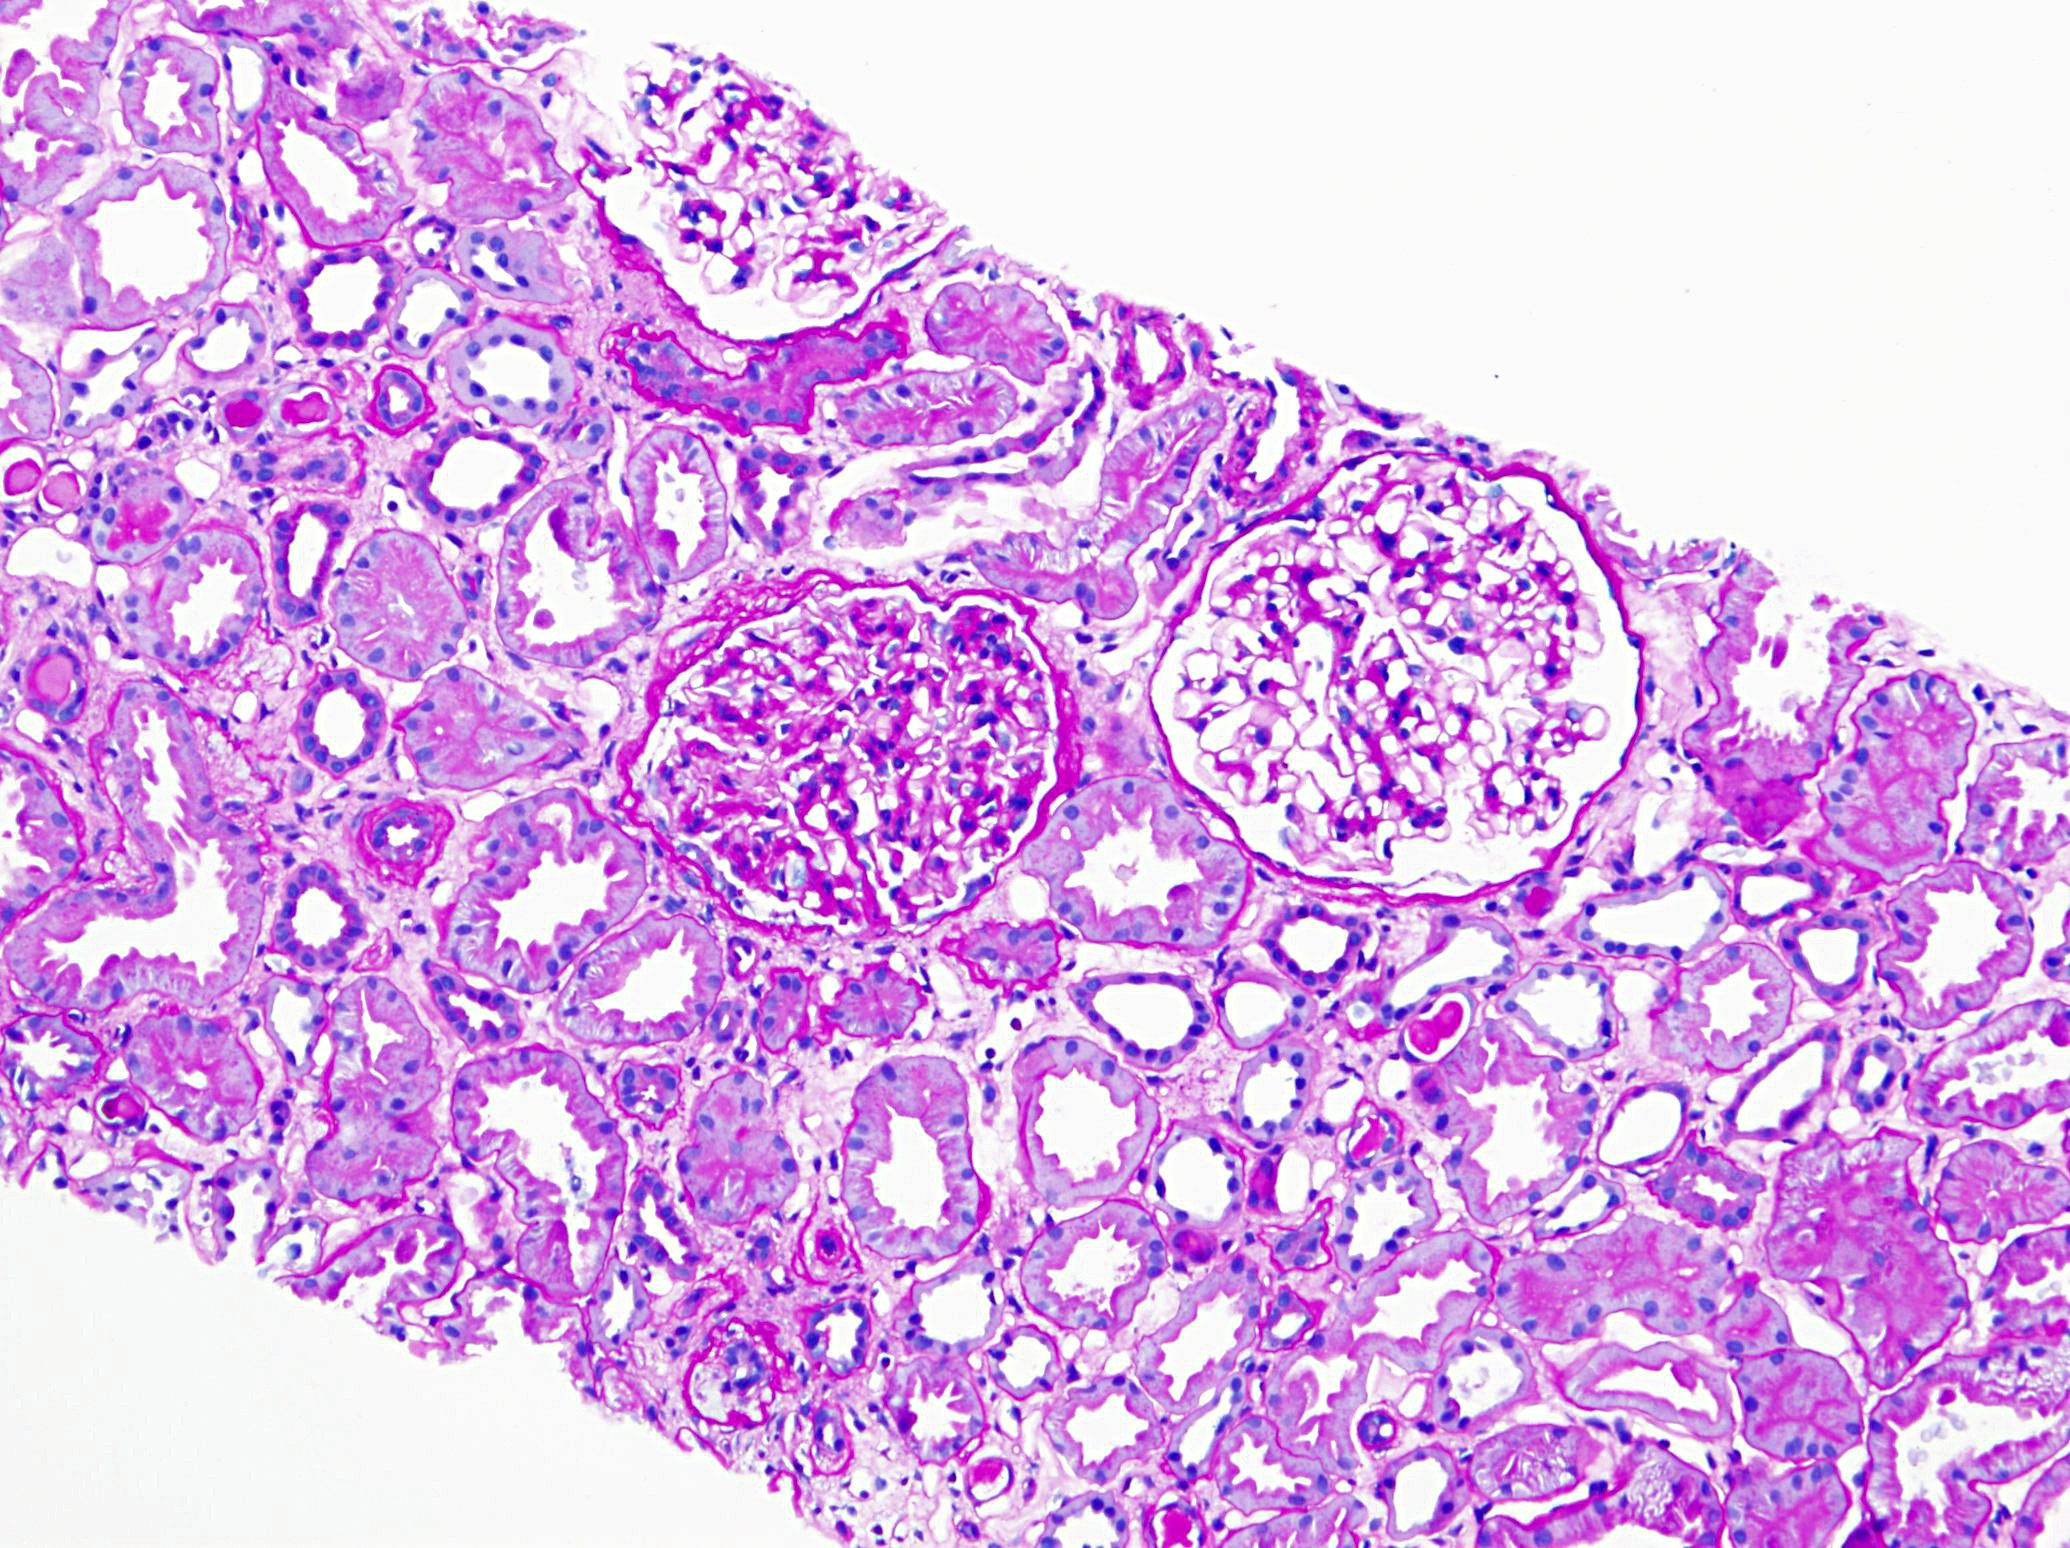

A 71-year-old man with long standing history of hypertension presented with increased serum creatinine of 3.4 mg/dL, detected during routine laboratory examination, with no associated symptoms. He was eventually seen by a nephrologist. A kidney biopsy was performed. The biopsy findings are shown in the following figures (Fig A & B: PASH stain, Fig C: Lambda- immunofluorescence stain, Fig D: Kappa- immunofluorescence stain and Fig E: Electron Microcopy of the proximal epithelial cell cytoplasm).

The diagnosis of monoclonal immunoglobulin deposition disease (MIDD) by renal biopsy often precedes other clinical evidence of dysproteinemia and is commonly the presenting disease, which leads to the discovery of multiple myeloma. The renal diseases most frequently associated with multiple myeloma/MGUS include; amyloidosis, light chain deposition disease (LCDD) and light chain cast nephropathy (LCCN). Less frequently reported is a light chain proximal tubulopathy (LCPT) characterized by kappa-restricted crystal deposits in the proximal tubular epithelial cells cytoplasm. These patients classically present with Fanconi syndrome in the setting of smoldering myeloma. Light chain proximal tubulopathy without crystal formation, on the other hand, is relatively rare and under recognized dysproteinemia related entity which by light microscopy shows nonspecific pattern of acute tubular injury with no significant casts or crystal formation (Fig A and B). However monoclonal staining of protein resorption droplets within proximal tubular epithelial cells, by immunofluorescence, provides clue to the diagnosis (Fig C and D). Electron microscopy shows increased lysosomes with irregular contours and mottled appearance within proximal tubular epithelial cells (Fig E).